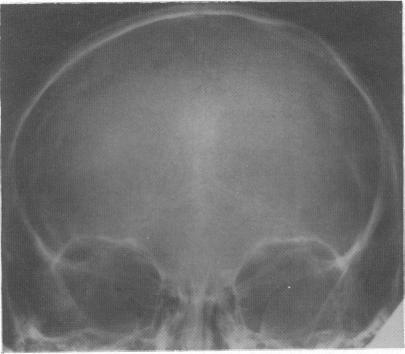

We studied eight patients with indolent gliomas. In all eight cases, despite characteristic radiological features, there was a delay in diagnosis because of misinterpretation of the initial computed tomogram. These tumours are an important cause of epilepsy of childhood, and surgery may well alleviate the epilepsy and possibly achieve a long term 'cure'. Therefore it is important that a diagnosis is made early and the lesion completely excised.